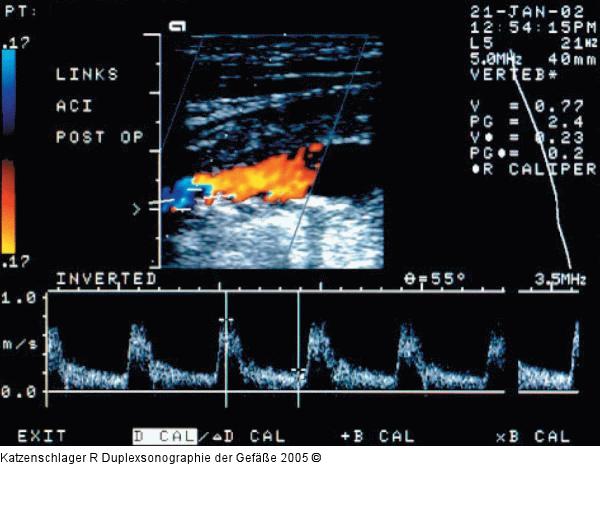

Abbildung 6: Duplexsonographie - Karotis

Hämodymisch nicht wirksame, eher fibröse, nicht glatte Plaques in ACI links (Vmax 0,7/0,2 m/sec) |